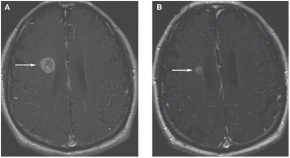

• For patients with non-small-cell lung cancer (NSCLC) and brain metastasis, effective treatment strategies are required because systemic chemotherapy is usually ineffective. Pan and colleagues present the case of a 73-year-old man who was diagnosed with NSCLC with brain metastasis, who carried anEGFR mutation and was managed with erlotinib and whole-brain irradiation. The authors discuss the treatment options for patients with metastatic NSCLC and propose erlotinib as an appropriate therapy for patients with a high probability of harboring classic EGFRmutations.